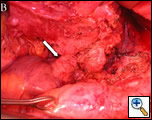

| Figure 1A Pre chemotherapy CT showing tumor at the confluence of the innominate veins (see arrows). | Figure 1B Pre chemotherapy CT showing tumor extending down into the right atrium (arrow). |

His physical examination was significant for head and upper extremity swelling, jugular venous distention without A or V waves, and superficial varices over the thorax. A computerized tomography (CT) scan (Figures 1A and 1B) demonstrated a mass in the mediastinum involving the superior vena cava (SVC) and extending into the right atrium. Echocardiography confirmed the intracardiac component. The patient was started on neoadjuvant therapy consisting of cisplatin, cyclophosphamide, and doxorubicin with plans for postoperative radiation therapy. A post chemotherapy CT scan demonstrated shrinkage of the mass (Figures 1C and 1D). A preoperative venogram confirmed the occluded SVC and well formed collaterals (Figure 2).